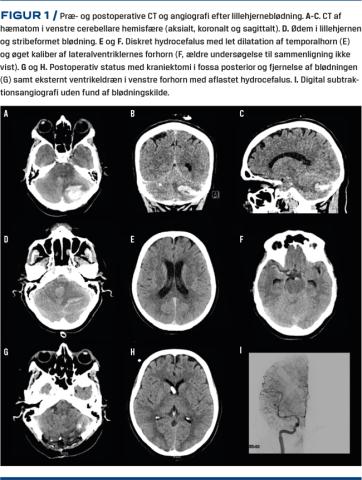

Postoperativt udviklede patienten over otte timer påvirket almentilstand, hovedpine, hæmatemese, hypertension (240/90 mmHg) og tiltagende somnolens. En akut CT af hjernen viste en stribeformet blødning i begge cerebellare hemisfærer, globalt lillehjerneødem og et samlet hæmatom i venstre cerebellare hemisfære (Figur 1A, B, C, D). Dette medførte hjernestammepåvirkning og begyndende obstruktiv hydrocefalus, men uden tegn til vævsherniering gennem foramen magnum (Figur 1E, F). Ved CT-arteriografi påviste man ingen intrakraniel karmalformation eller anden blødningskilde. Patienten blev akut overflyttet til Hjerne- og Rygkirurgisk Afdeling på Aarhus Universitetshospital, hvor hendes score på Glascow Coma Scale (GCS) var på 13, hun havde normalt spontant bevægemønster, parallelle øjenakser og små, lysreagerende pupiller. Man lagde akut et eksternt dræn for at aflaste den supratentorielle hydropcefalus (Figur 1H). To timer senere descenderede hun bevidsthedsmæssigt til en GCS-score på 9 og udviklede meningealia og blikdeviation mod højre. Hun blev intuberet, og man foretog akut og ukompliceret dekompressiv kraniektomi af fossa posterior med evakuering af blødningen, som var beliggende i en cerebellar fissur. Ved en postoperativ digital subtraktionsangiografi afkræftedes ligeledes en blødningskilde, og en postoperativ CT viste tilfredsstillende forhold (Figur 1G, H, I). Patienten blev ekstuberet dagen efter og overflyttet til et intermediært observationsafsnit. I efterforløbet havde hun smerter, ganesejlsparese, gangataksi og kognitiv dysfunktion, som normaliseredes i løbet af få dage. Det eksterne dræn blev seponeret, og hun blev udskrevet til genoptræning på syvende postoperative dag med beskeden gangataksi som eneste symptom.